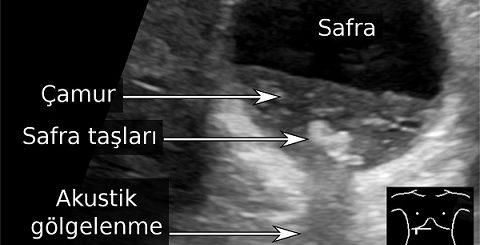

- Safra Üretimi:

- Safra, yağların sindirilmesi ve emilmesi için gereklidir.

- Kolesterol ve yağ asitlerinin atılımında kullanılır.